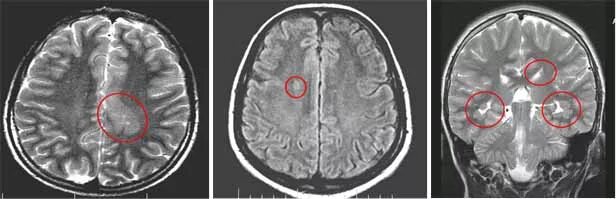

Диффузной биполушарной кортикальной атрофии